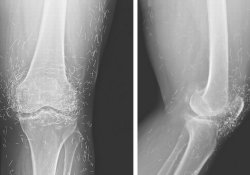

Мы сдали онко простаты, онко жкт, ФГСД, ирригоскопию, МРТ поясницы 2 раза, грудного отдела, мозга, флюорография весной,рентгены суставов ног, всех ног - патологий нет. Тоесть отец более менее проверен с головы до ног. Колоноскопию не хочет. Говорит устал. Онкологию все думали почти, но не нашли нигде, потому к онкологу не послали. Я была летом у онколога, но забыла сказать про похудение. Но он меня всеравно отправил к сосуд. хирургу. Но и там не помогло. Онколог сказал - при чем тут боли в ногах к онкологии. Дело в том, что отца кроме сильной боли в левой ноге сейчас ничего и не беспокоит. Ни малейшей боли в животе например. Может у вас будут еще какие-то идеи. Я напишу какие заболевания нашли и , что отец употреблял.